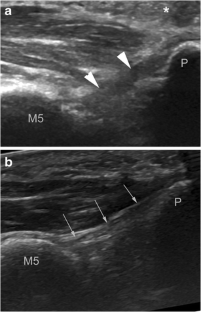

Fig. 3